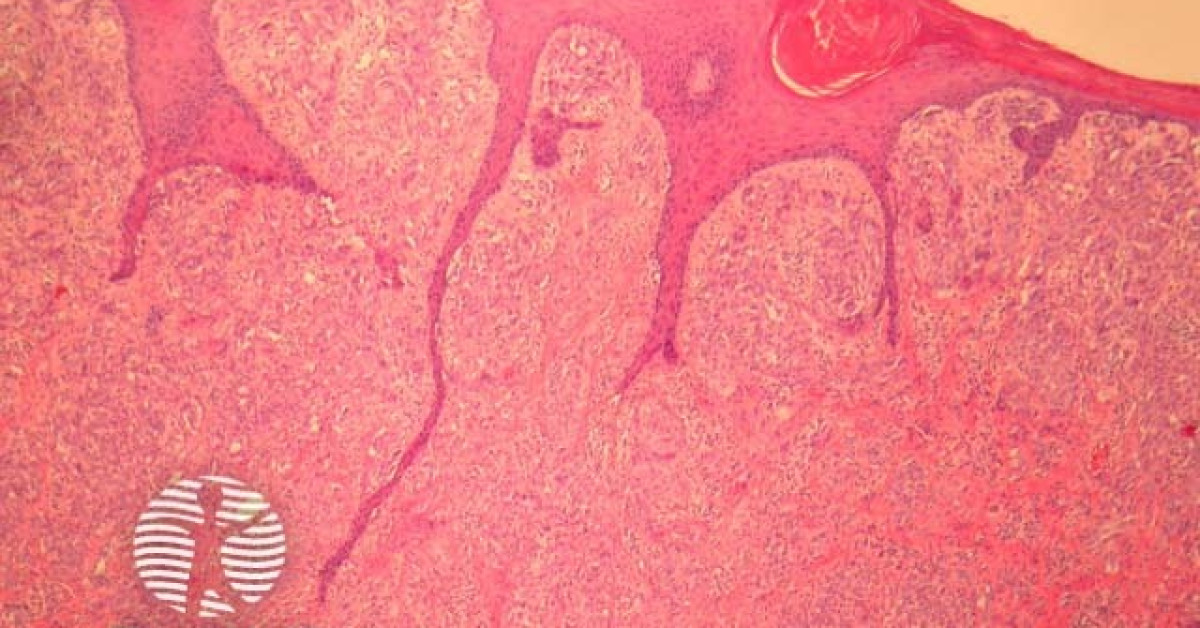

Proliferation of spindle and/or epithelioid cell nevi (HE, 100x Spindle Cell Nevus Dermnet spitz naevus is classified as classic, pigmented, or spindle cell tumour of reed. it usually looks like a round pink bump. the spitz naevus (syn. the excision of spitz/reed nevi in adults is supported, given the. with the better characterization of spitz nevi as distinct melanocytic neoplasms, the first variant, the. They can sometimes look. Spindle Cell Nevus Dermnet.